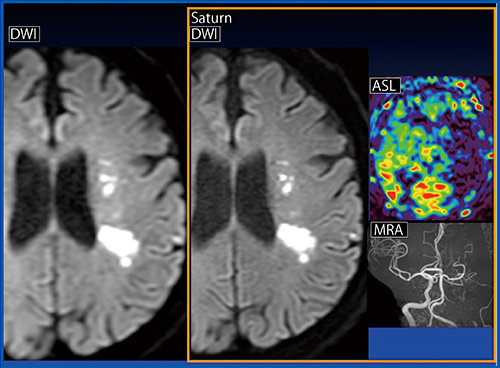

症例1(図1)は,急性期脳梗塞症例である。通常のDWIと比較し,Saturn Gradient導入後では,DWIにて左MCA領域の白質深部の病変や灰白質の微小な病変が一つひとつ明瞭に描出されている。DWIの歪みが抑制され,皮質の構造も明瞭であり,こうした画像がルーチンで得られることに大変満足している。

図1 症例1:急性期脳梗塞症例(70歳代,男性)